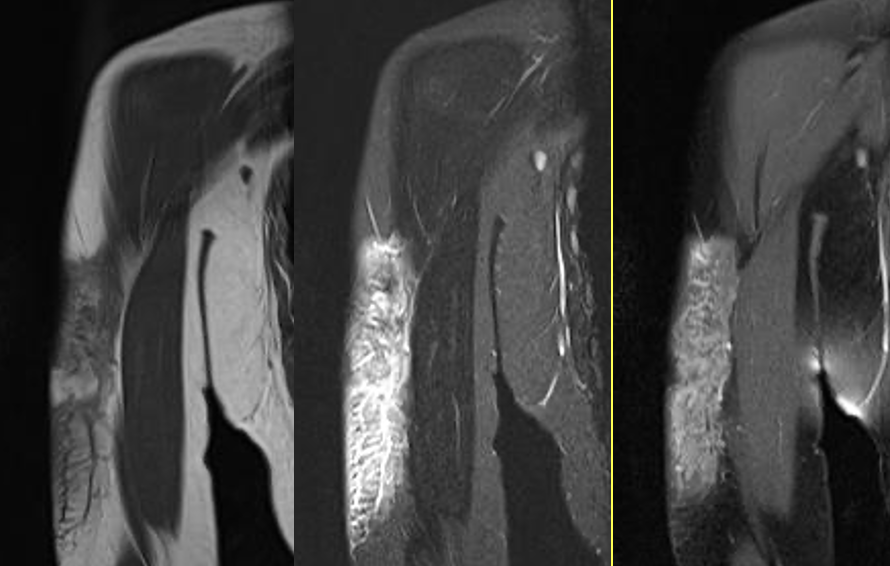

gout arthritis ( rid3567 )